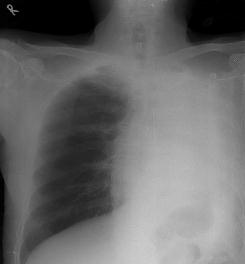

上周,32岁的余杭小伙张某因持续不好的感冒走进了邵逸夫医院的大门。大家都知道,感冒大多属于呼吸道疾病,拍胸片属于常规检查??赡玫搅顺9嫘仄幸缴枷帕艘惶?,不常规的事情发生了:从胸片上来看,他的左肺一片空白,是个白肺!看上去左肺就跟被“偷走”了一样。

随后的体检发现小张的两侧胸廓不对称,左侧胸廓明显塌陷,说明这种情况绝不是短时间才会形成。

什么情况才会引起一位身强力壮的年轻人左肺全部丧失而他本人又没任何察觉?带着疑问,呼吸内科陈恩国主任医师给他进行了支气管镜检查。

“我们检查发现,小伙子的左侧支气管完全堵塞了,其中一半是管壁塌陷,另一半是个球状的新生物。”陈恩国说。